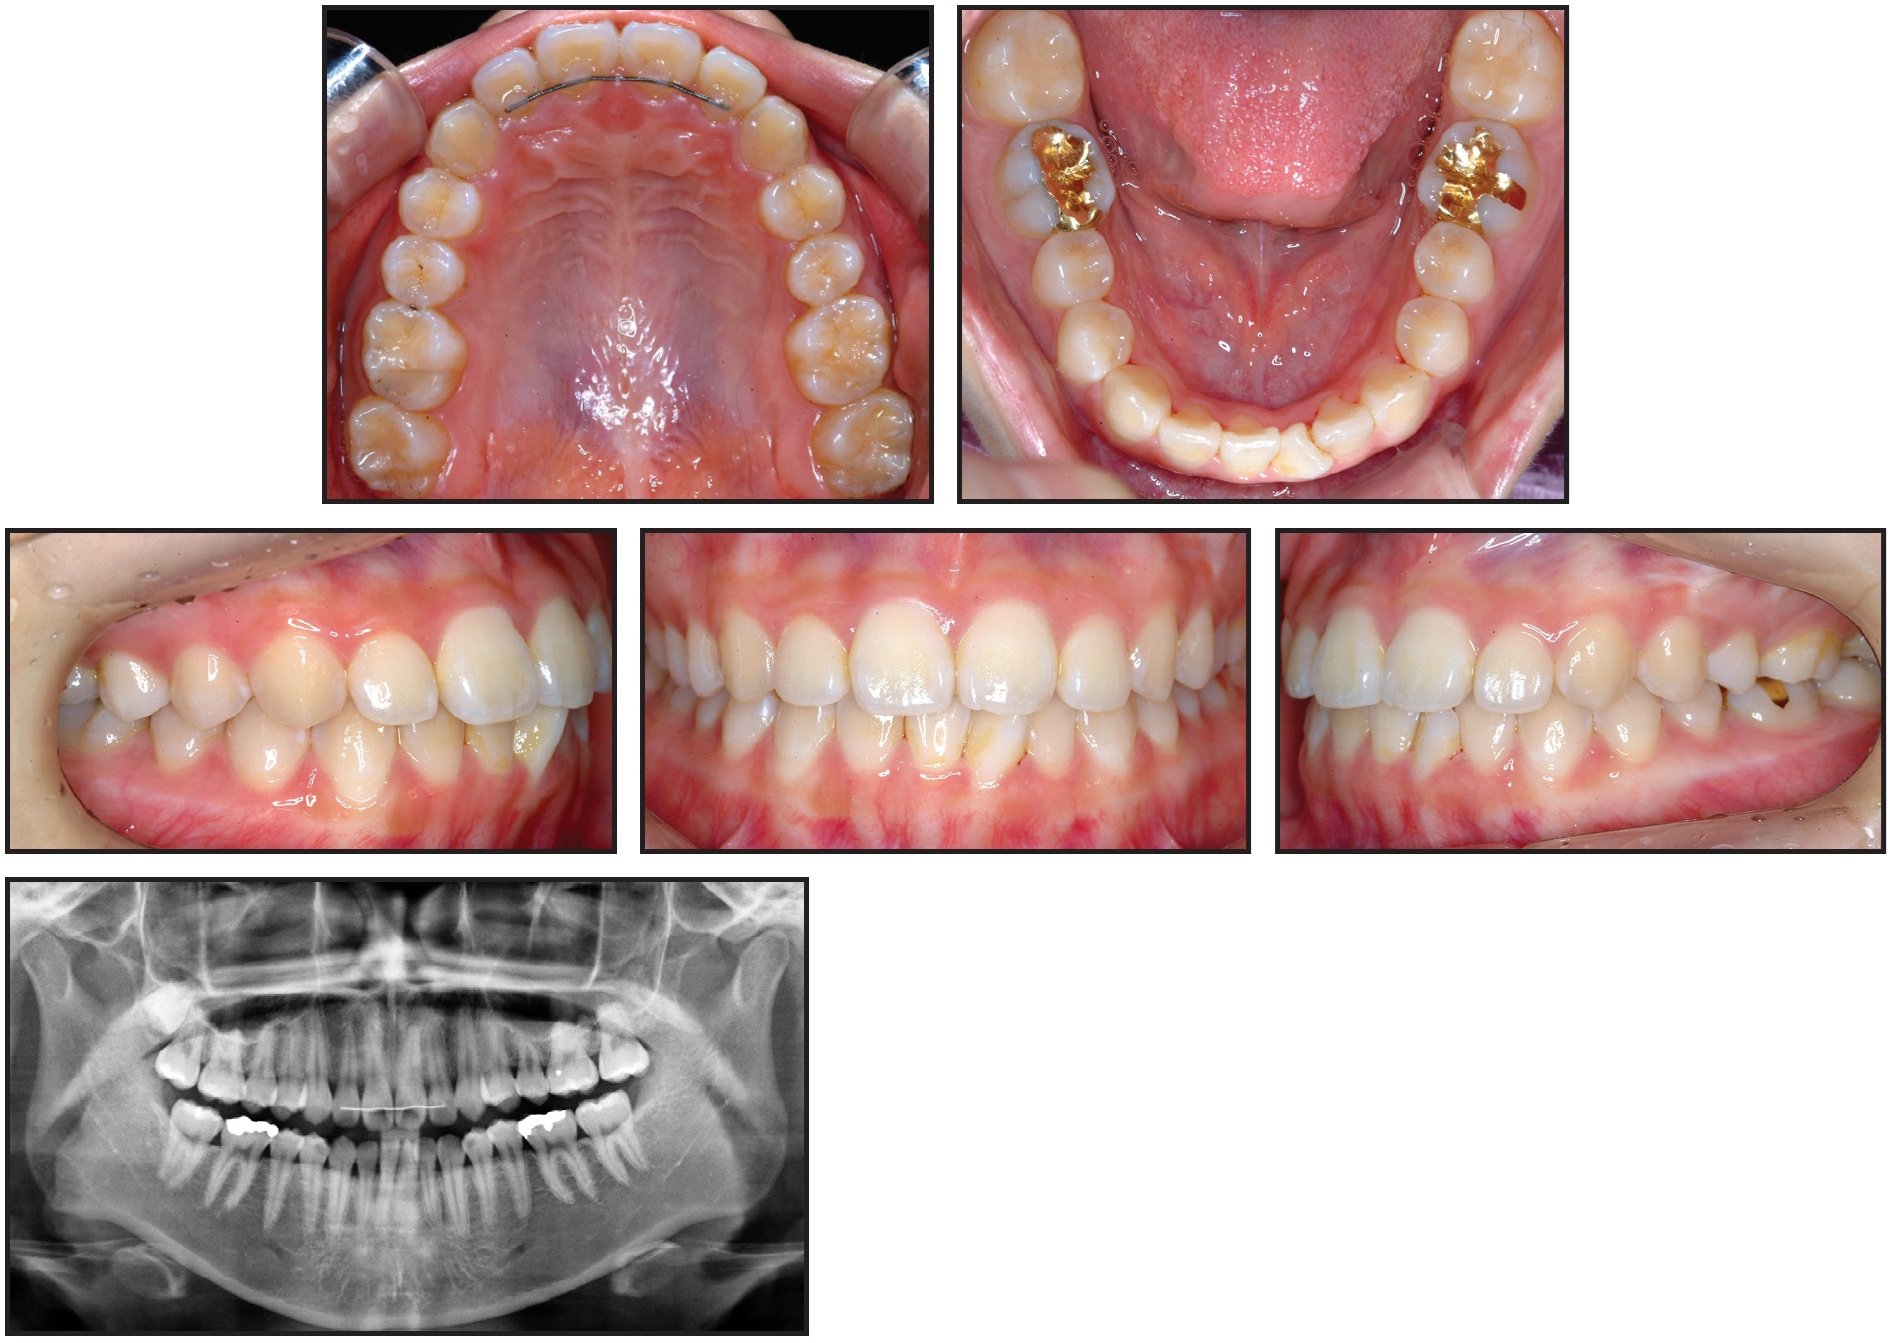

A 14-year-old female presented with the chief complaint of prolonged retention of a second deciduous molar (Fig. 1). She had bilateral Class I canine and molar relationships and a balanced facial pattern. A retained upper left second deciduous molar was found in the position of the missing second premolar. Radiography revealed an impacted and inverted upper left second premolar, with the crown facing toward the maxillary sinus floor.

Fig. 1 14-year-old female patient with prolonged retention of second deciduous molar and bilateral Class I canine and molar relationships before treatment.